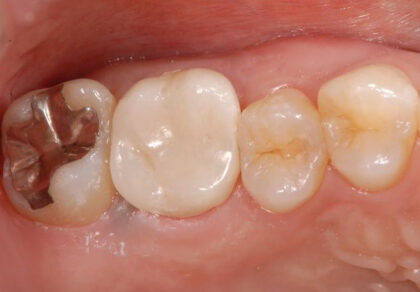

移植前

重度虫歯の右上6番の歯に、右上の親知らず(8番目)を移植しました。

移植後